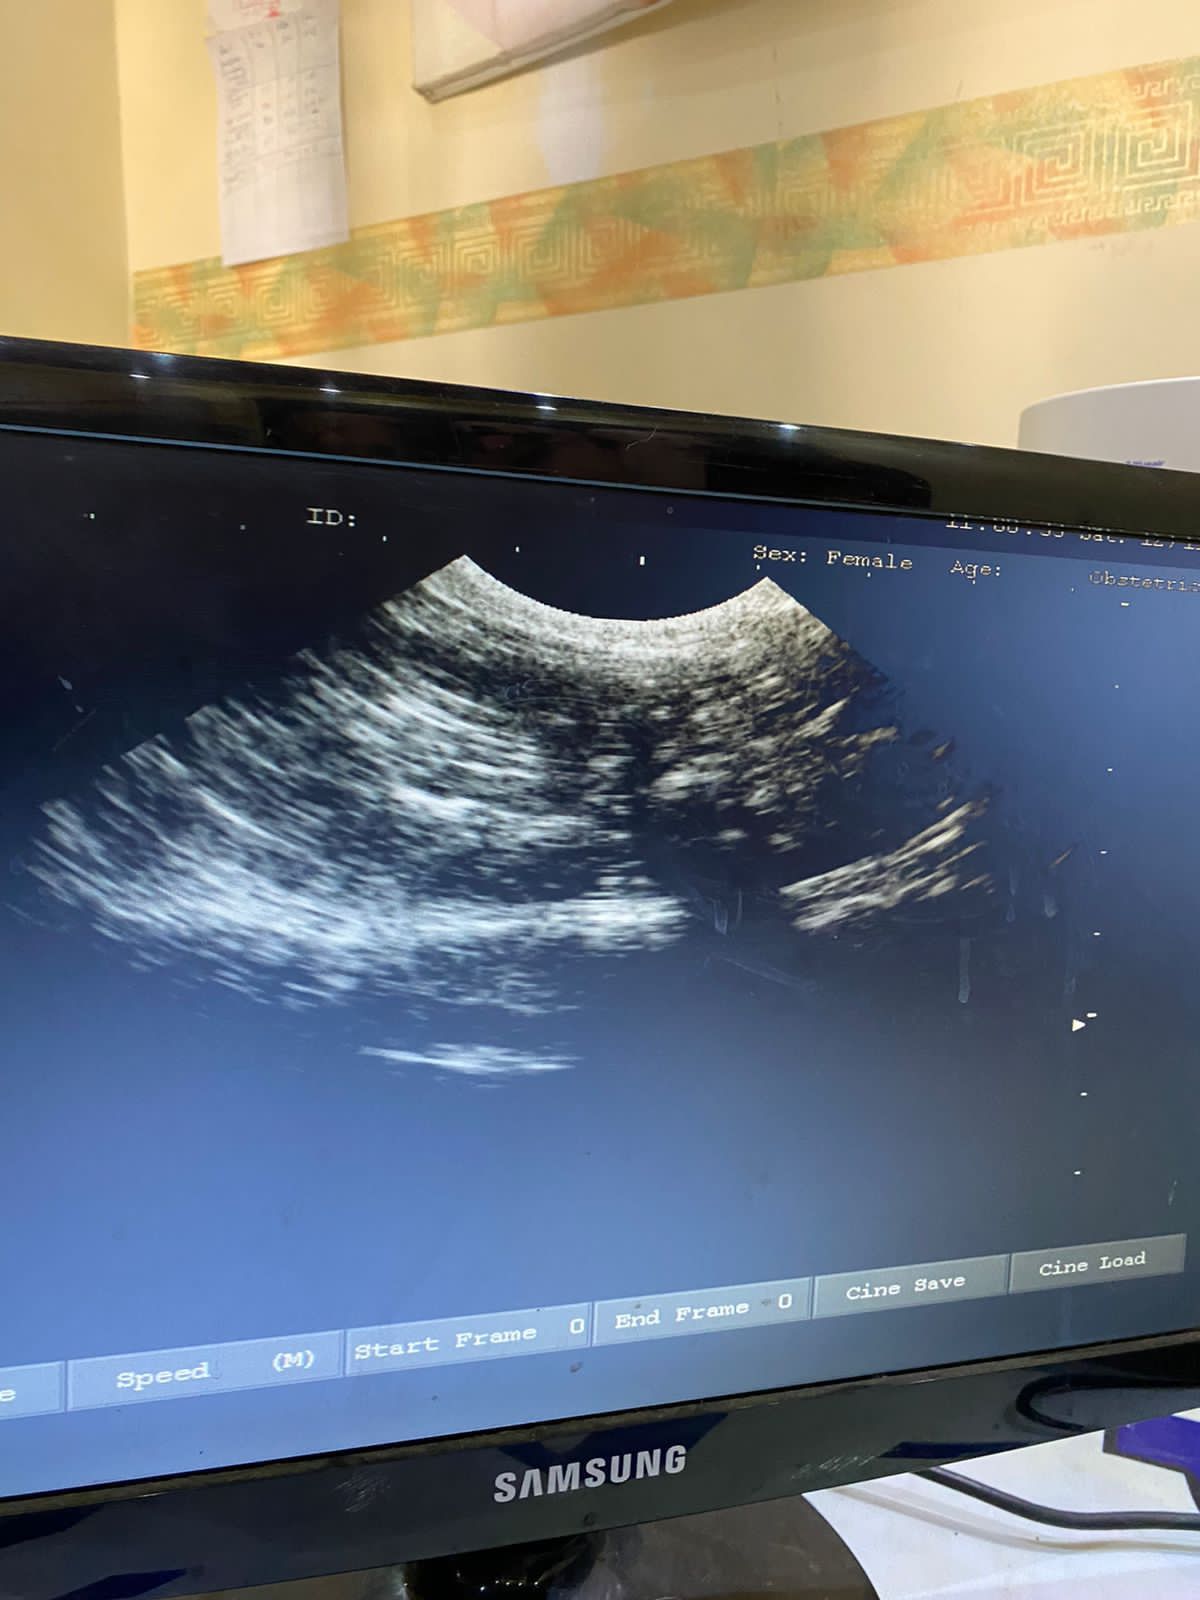

Ultrasound

Ultrasound is used for reasons, such as:

During pregnancy and fetal surgery

Diagnosis of gallbladder diseases

Assessment of blood flow

Needle guidance for biopsy or oncology

block check

Thyroid examination

Detection of genital and prostate problems

Evaluation of joint inflammation (synovitis)